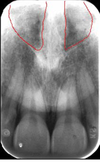

This is located palatal to incisors, pear-shaped opening; nasopalatine nerves and vessels

incisive foramen

incisive foramen

This leads to the incisive foramen; radioopaque margins, radiolucent center

incisive canal

This is a palatal radiolucent line between two processes running posteriorly from alveolar crest

median palatine suture

median palatine suture

This is a “V” shaped projection present in midline apical and central incisors; radiopaque

anterior nasal spine

anterior nasal spine